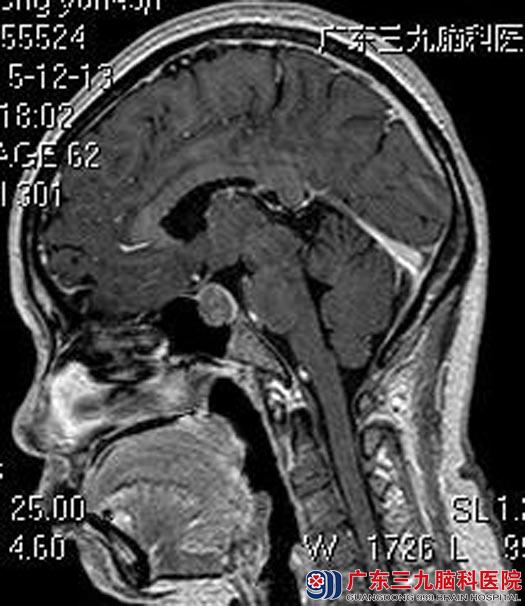

头颅MR检查显示:鞍区占位性病变,范围约1.50cm×0.98cm×1.74cm;鞍底轻度下陷,鞍隔膨隆,视交叉轻度受压,垂体柄受压右移。